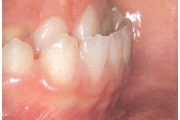

kaaries igemeäärel